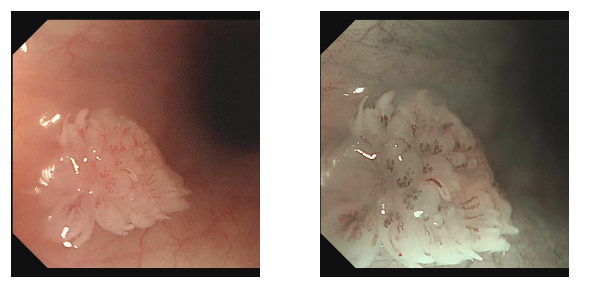

检查过程中,内镜医生有了意外发现:小张的食管部位长有一个形似花朵的乳头状瘤。吕主任介绍,食管乳头状瘤在临床中并不常见,尤其是在年轻男性群体中更为少见,其发病多与病毒感染相关,比如HPV病毒。幸运的是,发现及时,肿瘤尚处于早期阶段,医生随即为小张进行了内镜下切除术,整个过程顺利完成。

吕主任表示,像小张这样的案例并非个例。很多年轻人对消化道的轻微不适不以为意,觉得“忍忍就过去了”,殊不知一些看似普通的症状,可能是身体发出的健康警报。食管乳头状瘤虽然恶变概率相对较低,但如果长期忽视,也存在病变风险。而胃肠镜检查作为消化道疾病筛查的“金标准”,能够直接观察到食管、胃、肠道黏膜的细微变化,实现早发现、早诊断、早治疗。